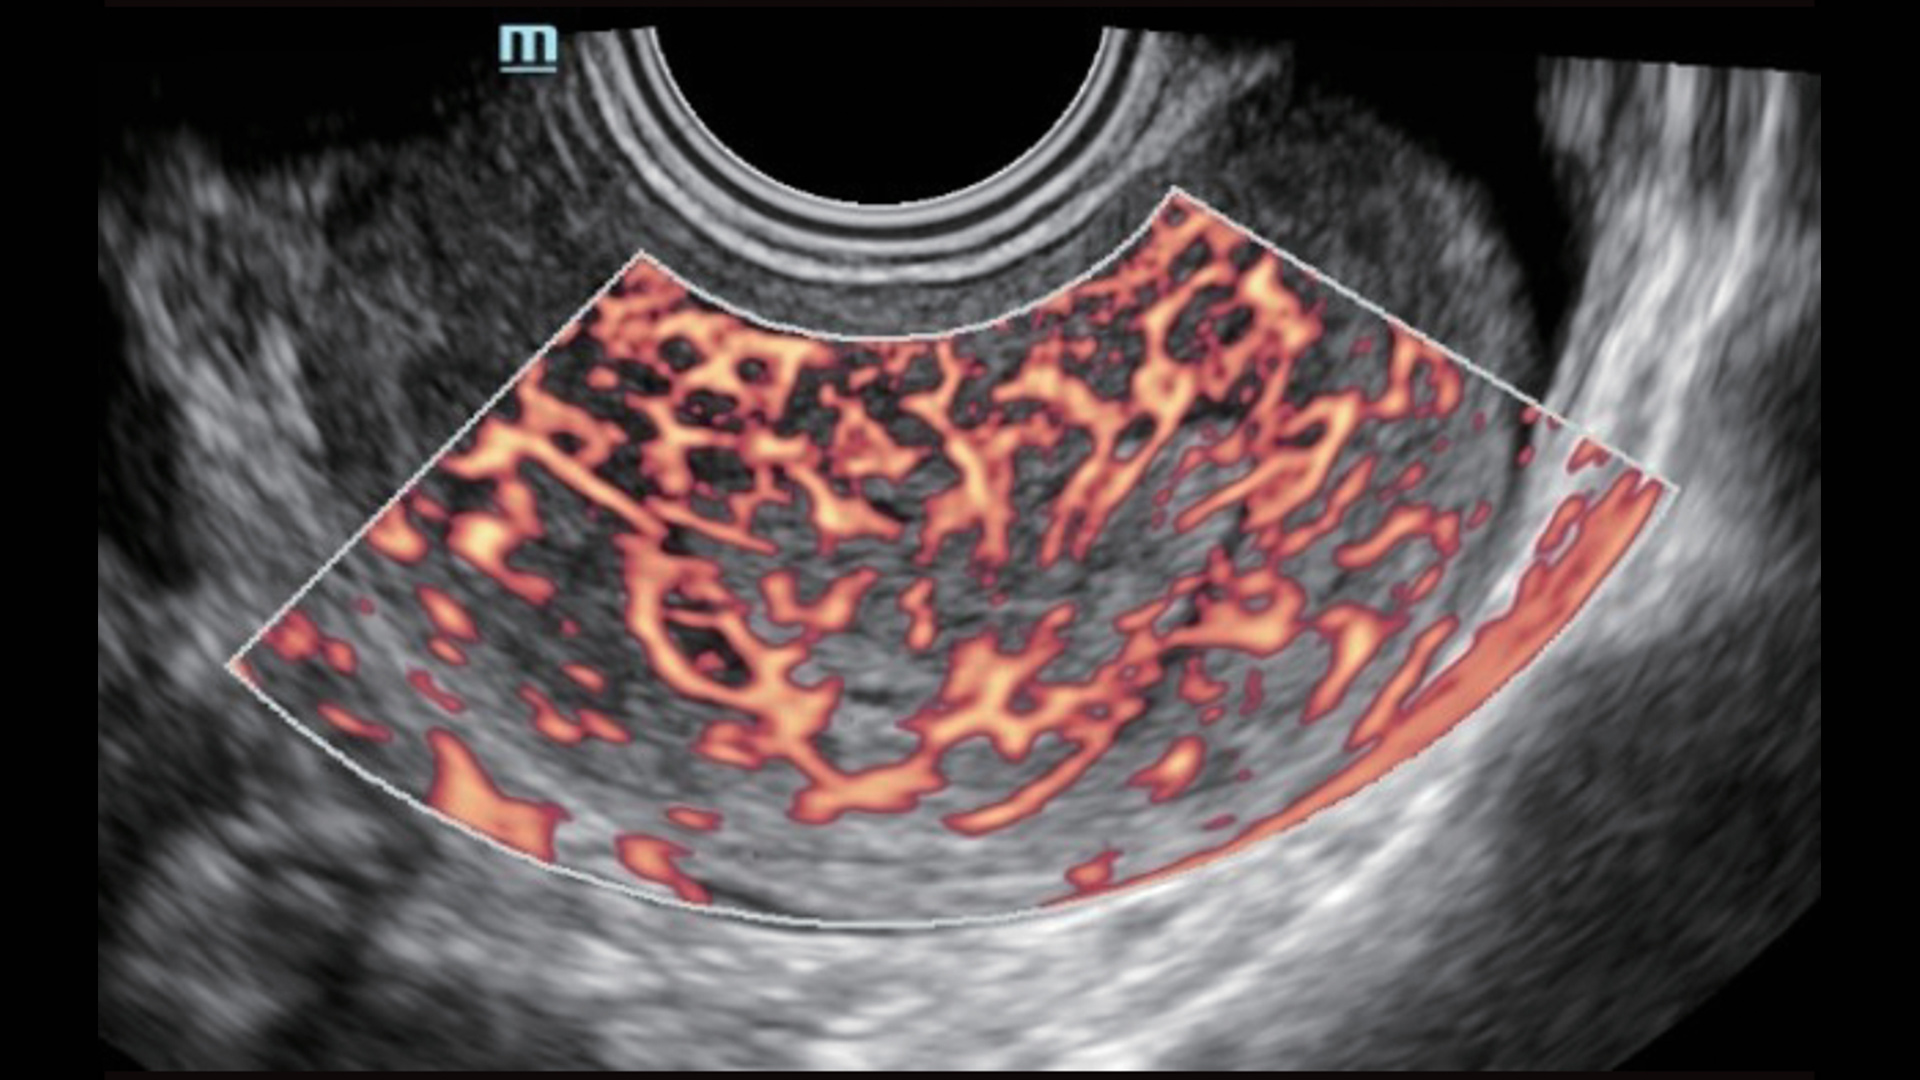

UMA (angiografia ultramicroscĆ³pica)

A tecnologia inovadora elimina as limita??es das tradicionais imagens com Doppler. Com resolu??o espacial e sensibilidade de fluxo ultra-altas, permite a detec??o de perfus?es de fluxos muito sutis e lentos, ampliando assim a aplica??o clĆnica da avalia??o qualitativa e quantitativa do ultrassom no cĆ©rebro fetal, rins, placentas, endomĆ©trios, ovĆ”rios etc.

UMA ā Fluxo uterino e endometrial

UMA 3D ā Fluxo sanguĆneo perifolicular